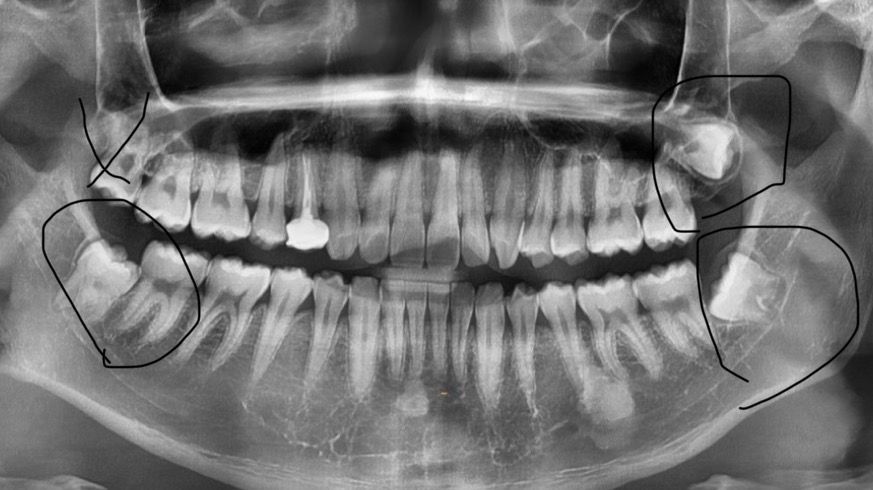

사진에 x표시는 뽑았고 남은 사랑니 3개중에 위에 사랑니는 안 빼도 된다고 합니다 나중에 문제 생기지는 않겠죠? 물혹같은거 생긴다는데 염려증있어서 또 걱정되네요.. 혀로 만져봤을때 위에 사랑니는 도저히 어디에 있는지 모르겠습니다 엄청 깊이 있는건가요..

사랑이의 경우에 매복되어 있고 주변 치아에 문제를 발생시키지 않는다면 매복되어 있는 사랑니는 발치하지 않아도 됩니다. 매우 드문 확률로 낭종 등을 형성할 수 있지만 주기적으로 검진을 받는다면 그런 가능성을 미리 확인할 수 있습니다.

네 잇몸뼈 속에 아예 매복되어 있기 때문에 당연히 육안으로나 혀로 만져봤을때 없는것처럼 느껴질 거고요.

빼지 않을 경우 물혹(낭)이 생길 가능성을 아예 배제할 순 없습니다만 또 그렇게 흔하진 않습니다.

6개월~1년 주기로 정기적으로 파노라마 엑스레이 찍으면서 검사해주면 됩니다.